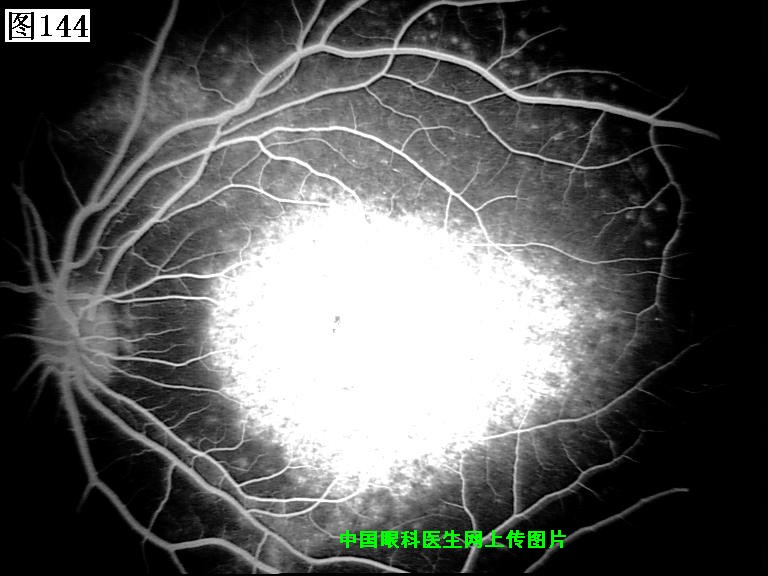

141 142 143 144